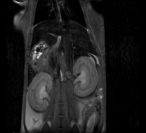

Small Animal Multimodal Imaging

Magnetic Resonance